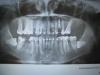

Doc Опубликовано 11 марта, 2011 Поделиться Опубликовано 11 марта, 2011 Здравствуйте! Мне 46 лет, заканчиваю ортодонтическое лечение, надо протезироваться в 3 местах.До сих пор не определилась с верхней челюстью с левой стороны(не хватает 4-ки)Ортопед предлагает либо имплант, либо мостик-консоль. Не знаю что выбрать, тк имплант (еще один)ставить особо и времени нет (снятие брекетов назначено через неделю), а если ставить, то чтоделать с 5-ой и 6-ой - депульпированы, ставить на них коронки или так оставить.И если сделать мост на 6-5-4 консоль, то какой срок службы такого моста и что мне потом надо будет делать с 5-ой и 6-ой - удалять? Судя по всему Вы снимок вывесили задом наперед. Имплантат у Вас стоит справа, как я понял? Ну а слева, судя по снимку, места для имплантата маловато. Окончательный вывод можно сделать только после личного осмотра, но по снимку кажется именно так. В Вашем варианте нужно и пятерку и шестерку под ВКВ, а дальше врач пусть решает сам, в принципе, консоль это не очень хорошо, но в Вашем случае позволително. Удалять впоследствии пятерку и шестерку с какого перепуга?? Если все будет сделано грамотно и правильно, то эти зубы еще много-много лет простоят. Ссылка на комментарий

Doc Опубликовано 12 марта, 2011 Поделиться Опубликовано 12 марта, 2011 Огромное спасибо! Просто при обсуждении вариантов ортодонт сказал, что консоль работает как рычаги со временем 5-ка и 6-ка как бы будут "отжиматься", ну т.е. как я поняла просто со временем выпадутчто ли? Все зависит от ситуации. В принципе консоль это неправильная конструкция, когда много места для нормальной коронки. В Вашем случае (если это снимок сделан после ортодонтического лечения, а не во время) места для имплантата и полноценной коронки скорее всего нет, а следовательно консолька будет маленькая и два зуба ее вполне удержат. Кроме того, вряд ли Вы будете грызть ею орехи и сухари, ретейнеры Вам не позволят. Так что либо давайте свежий снимок, либо на Вас нужно смотреть лично. Doc, интересный случай кстати.. Что думаете по поводу 8к, на удаление их? Это только в личке. Ссылка на комментарий

AspiJET Опубликовано 13 марта, 2011 Поделиться Опубликовано 13 марта, 2011 (изменено) Добрый день! Снимок свеженький от 11 февраля (день постановки импланта), как сказала мой ортодонт-двигать уже некуда и нечего не будем.Насчет 8-ок - просто ооох!!!! консультировалась у 4 хирургов, 3 советуют не трогать, раз дожила с нимидо такого возраста и они не беспокоют, то и не надо. Собственно, я и сама не особо рвусь их удалять, ткдля меня эт будет очень больно и травматично, тем более что их надо реально из челюсти выпиливать икак потом восстановление костной ткани пойдет тож неизвестно. А Ваше мнение?Добрый день! Тяжело конечно виртуально что-либо советовать, но с 8ми вашими действительно все непросто, оставлять их или нет, такое решение должен принимать хирург. Если снимок свеженький, как вы говорите, то место под коронку на импланте и под имплант на верхней челюсти нет судя по снимку. Изменено 13 марта, 2011 пользователем AspiJET Ссылка на комментарий